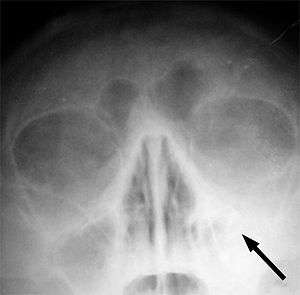

| Left-sided maxillary sinusitis marked by an arrow. Note the lack of the air transparency indicating fluid in contrast to the other side. | |